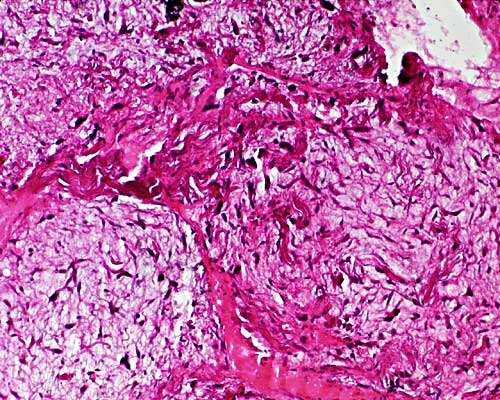

CASE 2

Male, 47 years old with painless,

slow growing nodule of approximately

3 cm in largest diameter, located in the

subcutis of the shoulder. No history of

trauma was recorded at that level.

Clinical diagnosis: lipoma.

Gross: Masses of gray mucoid material

admixed with some fragments of adipose tissue.

Microscopy: Five images.

Immunohistochemical study:

Positive for CD-34.

Negative for keratins, protein S-100,

vascular markers, MIB-1 and protein p53.

Magnification 10x